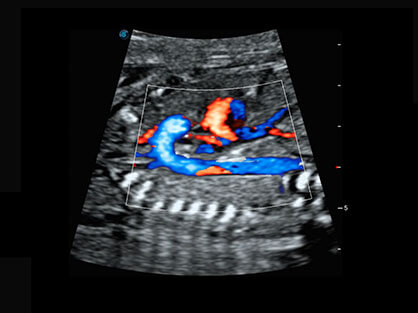

通过对组织运动信息、血流信号及背景噪声进行准确智能的阈值判定,高效提取出微弱血流信号,获得高灵敏度和空间分辨率的血流图像,为临床提供更加真实和丰富的诊断信息。

可同时显示组织结构表面和内部的轮廓信息,达到透视效果,为临床提供更丰富的诊断信息。